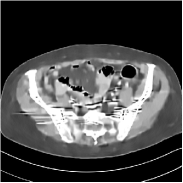

Fig. 3 illustrates the image evolution over SUPER layers (i.e., with evolving network weights in the iterative reconstruction process) for one test case, when using SUPER-WRN-ULTRA. It is apparent that in the early SUPER layers, the proposed SUPER-WRN-ULTRA method mainly removes noise and artifacts, while later SUPER layers mainly reconstruct details such as the bone structures shown in the zoom-in box. A similar behaviour is observed with FBPConvNet-based SUPER methods, which are shown in the supplement (Figs. 13 and 14).

Refer to caption Refer to caption Layer 1RMSE =27.44 HURefer to caption Refer to caption Layer 5RMSE = 26.03 HU

Refer to caption Refer to caption Layer 11RMSE = 25.91HURefer to caption Refer to caption Reference

Figure 3: Image evolution over SUPER layers using the SUPER-WRN-ULTRA method. RMSE values are also indicated.